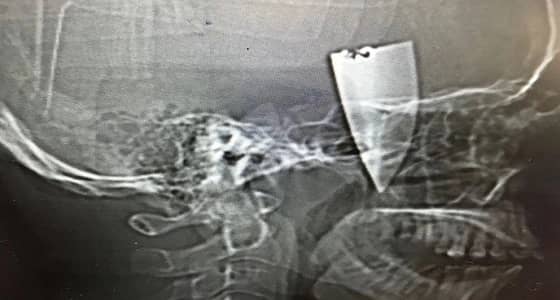

جراحة ناجحة لشاب مصاب في وجهه بمجمع الملك فيصل بالطائف

نجح بفضل الله فريق جراحي بمجمع الملك فيصل الطبي بمحافظة الطائف في إستخراج نصف سكين حادة من وجه شاب عشريني. بعد أن وصل في حالة طارئة إلى قسم الطوارئ ، حيث تم الكشف عليه واتضح انه مصاب بجرح قطعي في الجهة اليمنى من فروة الرأس بطول 10سم,وتم على الفور إجراء الاسعافات الاولية ، وبإجراء فحوصات إشعاعية إتضح وجود جسم غريب داخل مدفون بالأنسجة ، وممتد من فروة الرأس حتى اسفل القوس الوجيني الايمن مع إنعدام الحركة من الفك السفلي وأدخل الشاب إلى غرفة العمليات ، وقام فريق جراحي مكون من أطباء جراحة ووجه وفكين بالعمل على إستخراج الجسم الغريب الذي إتضح أنه عبارة قطعة نصف سكين طولها 7سم..وتمت العملية دون أي مضاعفات تؤثر على صحة الشاب.